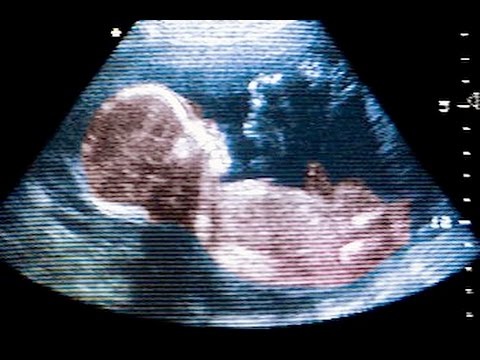

1. Первая эрекция у человека происходит еще в утробе матери

Это может показаться невероятным, но по данным исследователей Medical News Today, при ультразвуковом исследовании утробы матери часто у плода обнаруживается эрекция. Согласно исследованиям 1991 года эрекция у плода может происходить несколько раз в час!